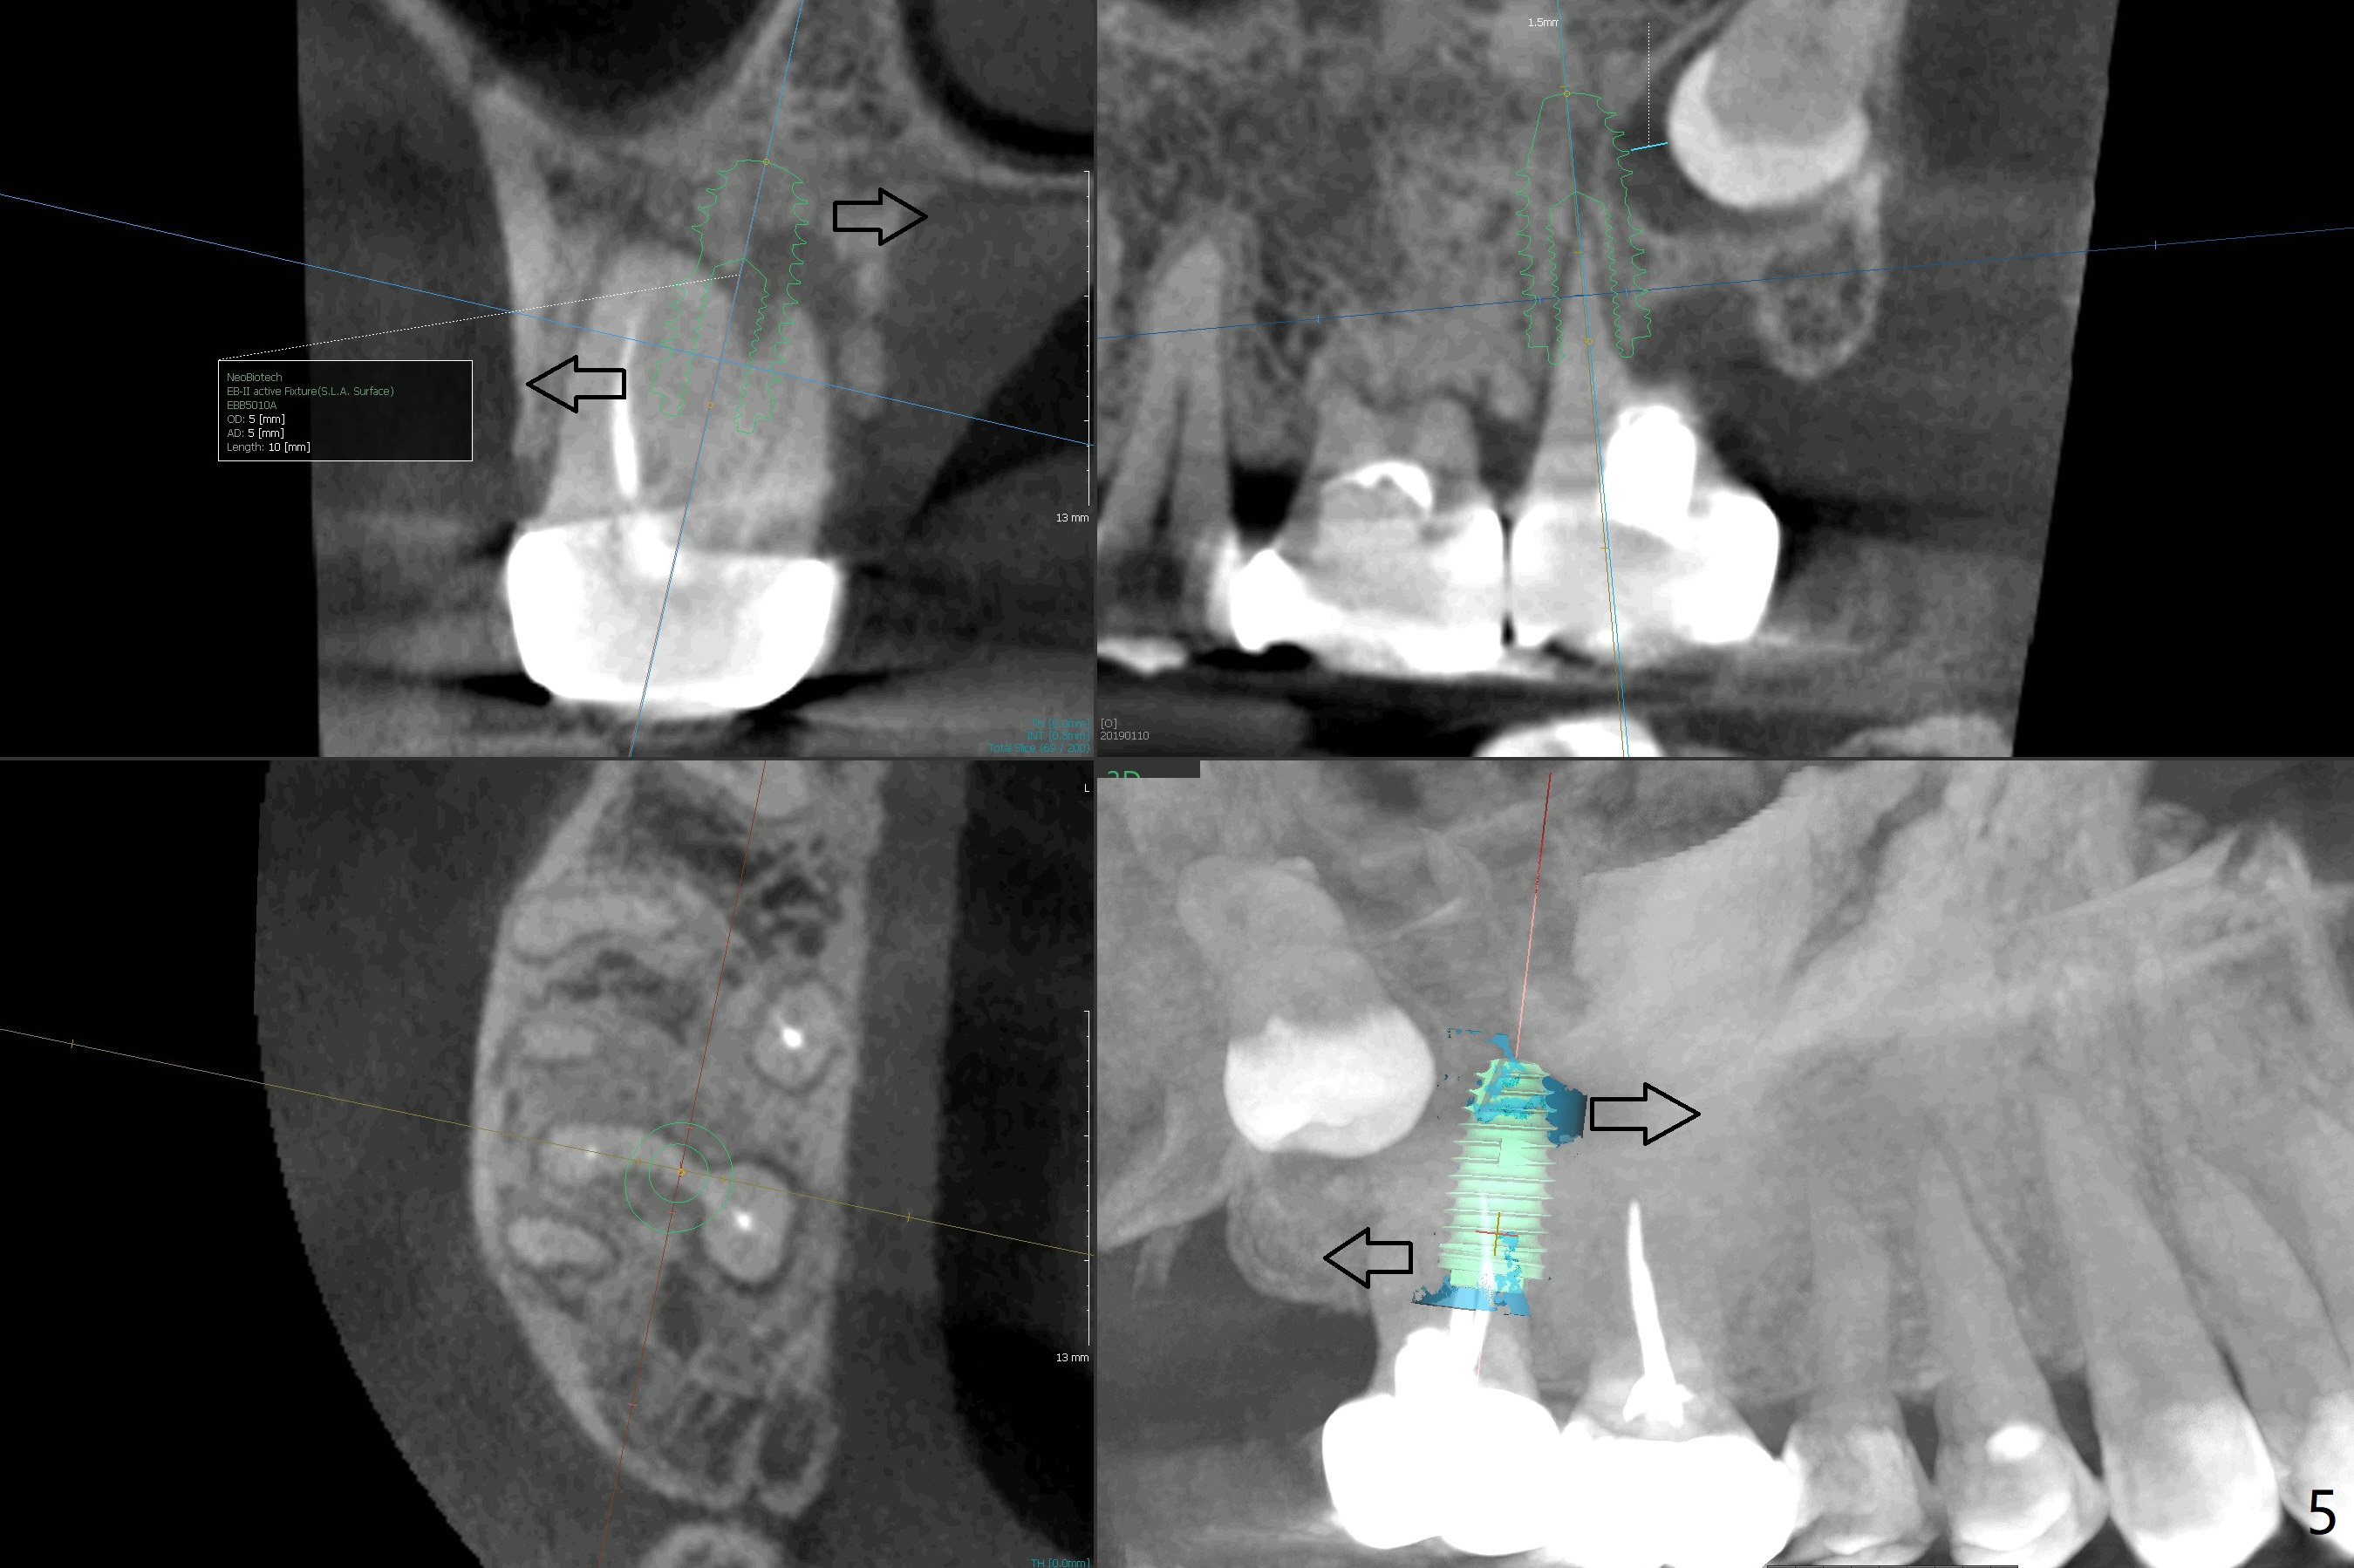

The tooth #1 should have been extracted buccodistally (Fig.3,4). Three or 4 months later, a 5x10 mm implant could be placed distopalatally superiorly to avoid removing the tooth #1 with ~ 1.5 mm clearance (Fig.5). To place an implant in orthopedic manner, the tooth #1 will be removed, while the implant should be longer (5x13 mm) to engage the bone superior to the socket of the tooth #1 (Fig.6).

The socket of #2 heals 13 days postop; it appears that the bone graft remains in place (Fig.7,8 *). The patient is instructed to return in 3-4 months for impression and CT for guide. The socket heals 4 months postop (Fig.9,10). She plans to have implant next year, since she wants to add another insurance. The patient returns for implant without removal of the third molar 2 years 4 months post socket preservation (Fig.11). A 5x7.3 mm implant can be placed without invading the sac of the impacted third molar (Fig.12). In fact the lab has a better plan. A lump of bone forms in the previous socket 1 year 4 months postop (Fig.13 *). The ridge is wide and dense (Fig.14). A narrow implant placed oblique could be longer (Fig.15), as compared to a wide, short one (Fig.12).